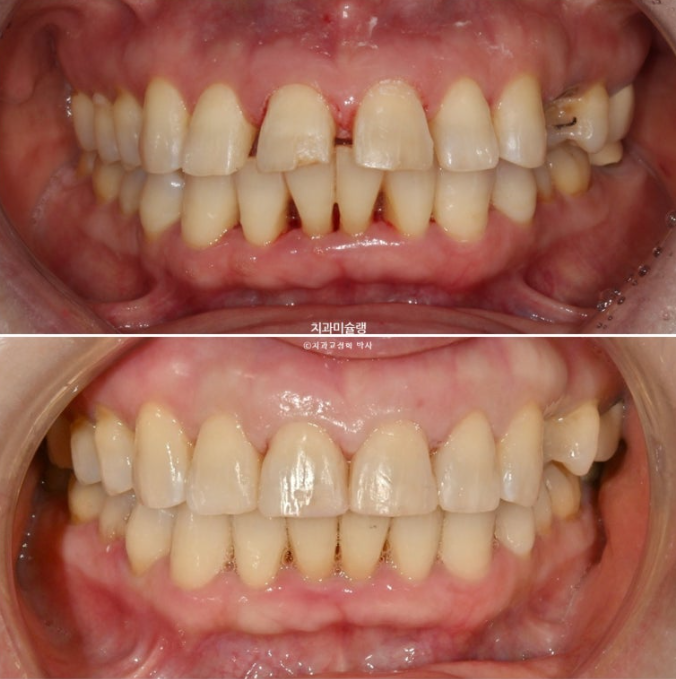

이제 전후 비교해보겠습니다.

24.07~26.01

앞니 각도의 개선이 눈에 띕니다.

아래 앞니는 치간삭제와 함입으로 위 앞니 사이사이 벌어진 공간을 이용하여 뻗친 각도와 골출을 개선하였으며

위 아래 앞니 각각 1.5-2mm 가량 뒤로 들어갔습니다.

1년 반 치료기간동안 뻗쳐있던 위 아래 앞니 각도가 개선이 되니 입술도 좀 더 편하게 다물립니다.